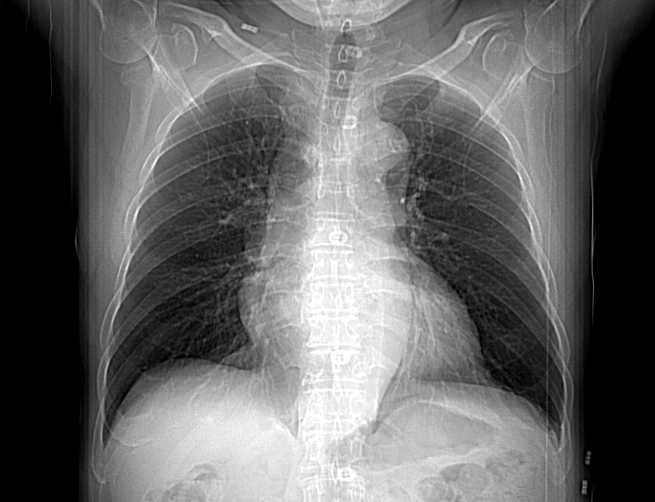

image (1).png

1년 전 흉부 엑스레이 VS 1년 후 흉부 엑스레이

폐암은 암 사망률 1위의 질환으로 많은 이들이 두려워한다. 어떤 질환이든 빨리 발견하는 것이 예후에 중요하다. 폐암 역시 그렇다. 우리는 건강검진 목적으로 해마다 찍은 흉부 엑스레이를 찍지만, 폐암을 조기 진단하는 검사법이 아니다.

2019년 12월에 보고된 한 연구에 의하면 폐암의 증상이 있는 사람이 흉부 엑스레이로 폐암을 진단받을 확률은 80%에 불과했다. 나머지 20%는 흉부 엑스레이에서 폐암을 찾지 못했다. 5명 중 1명은 폐암 증상이 있어도 엑스레이로 폐암을 진단받지 못했다. 이들은 폐암의 증상이 있는 경우였으므로, 증상이 없는 초기 폐암을 엑스레이로 진단하는 것은 극히 드문 일이다.

폐암은 빨리 자라는 암으로 폐암의 부피가 두 배로 커지는 데 걸리는 기간은 98일 (중앙값 기준)이다. 짧게는 한 달 만에 두배로 커지기도 한다. (소세포 폐암 30일, 편평 상피세포암 100일, 선암 180일) 이런 이유로 폐암을 진단받은 사람의 경우 65%에서 1년 이내 선별 검사에서 엑스레이를 찍었을 때 암이 없었다는 연구 결과도 있다.

폐암의 병변 특성상 흉부 엑스레이에 드러나지 않을 수 있다. 특히 암의 직경이 1CM 미만의 암의 경우 누락될 가능성이 높다. 만약 폐암이 상엽에 있거나 갈비뼈, 폐혈관, 심장과 같이 해부학적으로 겹치는 부위에 있다면 엑스레이로 진단이 어렵다. 그밖에 미숙련자와 영상 판독 실력이 부족한 경우도 폐암 진단의 누락 원인이 되기도 한다.